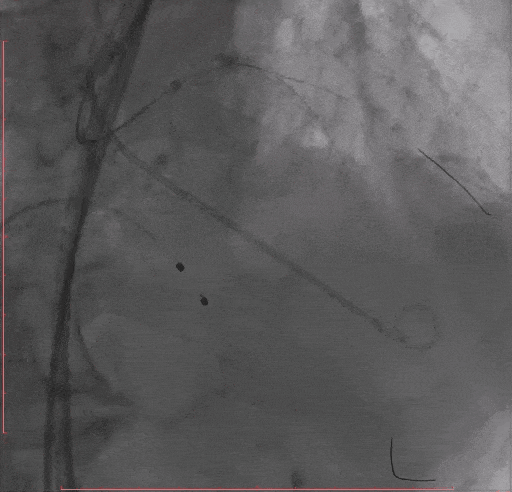

Step 9. 患者出现心衰,血流动力学不稳,予以IABP植入

术后复查超声心动图:人工瓣膜功能正常,主动脉瓣峰值流速179m/s,平均压差7mmHg,未见瓣周漏。

4.患者冠脉三支病变+主动脉瓣重度狭窄,手术过程中对手术团队的配合、术中如何保证血流动力学稳定提出了更高的要求。患者瓣膜释放后的循环不稳定,考虑此人术前已有失代偿经历,心脏储备差,旋磨、LM支架、高速起搏和瓣膜释放对心脏造成的打击引发泵衰竭,心肌处于顿抑状态,立即使用IABP进行辅助,让心脏得到喘息的机会,术后第二日成功拔除IABP,患者恢复好。